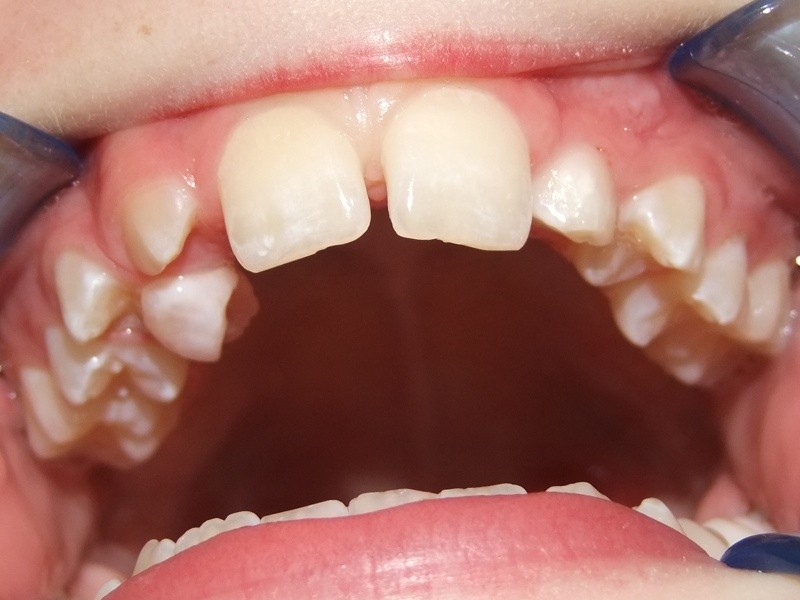

Na behandeling